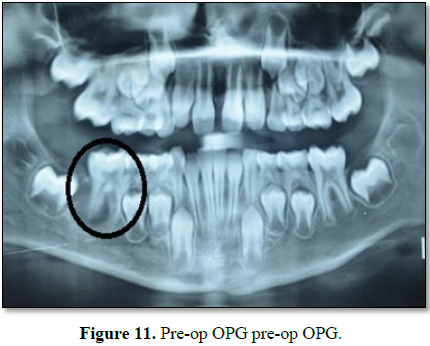

An 8 year old girl came with complain of pain

and swelling in lower left region of face since few months (Figure 1).

It relieves on taking medication but reoccur as soon as medication stops.

Patient has no relevant past medical or dental history. On oral examination

nothing suspicious was found. Patient had good oral hygiene. Patient was

advised for OPG. OPG revealed presence of radiolucency wrt to 36 and 46.

Patient complained swelling only but OPG revealed similar lesion on the other

side also which was not known to patient or parents as it was asymptomatic (Figure

2).